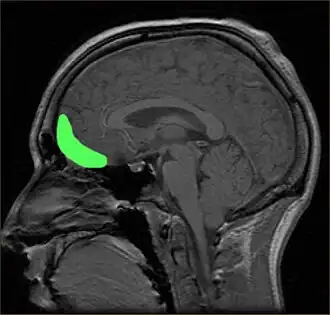

Dysfunctions in the prefrontal cortex and amygdala regions of the brain have been associated with specific learning impairments in psychopathy. Damage to the ventromedial prefrontal cortex, which regulates the activity in the amygdala, leads to common characteristics in psychopathic individuals.[75] Since the 1980s, scientists have linked traumatic brain injury, including damage to these regions, with violent and psychopathic behavior. Patients with damage in such areas resembled "psychopathic individuals" whose brains were incapable of acquiring social and moral knowledge; those who acquired damage as children may have trouble conceptualizing social or moral reasoning, while those with adult-acquired damage may be aware of proper social and moral conduct but be unable to behave appropriately. Dysfunctions in the amygdala and ventromedial prefrontal cortex may also impair stimulus-reinforced learning in psychopaths, whether punishment-based or reward-based. People scoring 25 or higher in the PCL-R, with an associated history of violent behavior, appear to have significantly reduced mean microstructural integrity in their uncinate fasciculus—white matter connecting the amygdala and orbitofrontal cortex. There is evidence from DT-MRI of breakdowns in the white matter connections between these two important areas.[76][77][78]

Researchers have linked head injuries with psychopathy and violence. Since the 1980s, scientists have associated traumatic brain injury, such as damage to the prefrontal cortex, including the orbitofrontal cortex, with psychopathic behavior and a deficient ability to make morally and socially acceptable decisions, a condition that has been termed "acquired sociopathy", or "pseudopsychopathy".[85] Individuals with damage to the area of the prefrontal cortex known as the ventromedial prefrontal cortex show remarkable similarities to diagnosed psychopathic individuals, displaying reduced autonomic response to emotional stimuli, deficits in aversive conditioning, similar preferences in moral and economic decision making, and diminished empathy and social emotions like guilt or shame.[156] These emotional and moral impairments may be especially severe when the brain injury occurs at a young age. Children with early damage in the prefrontal cortex may never fully develop social or moral reasoning and become "psychopathic individuals ... characterized by high levels of aggression and antisocial behavior performed without guilt or empathy for their victims". Additionally, damage to the amygdala may impair the ability of the prefrontal cortex to interpret feedback from the limbic system, which could result in uninhibited signals that manifest in violent and aggressive behavior.[76][87]

A 2008 review by Weber et al. suggested that psychopathy is sometimes associated with brain abnormalities in prefrontal-temporo-limbic regions that are involved in emotional and learning processes, among others.[169] Neuroimaging studies have found structural and functional differences between those scoring high and low on the PCL-R in a 2011 review by Skeem et al. stating that they are "most notably in the amygdala, hippocampus and parahippocampal gyri, anterior and posterior cingulate cortex, striatum, insula, and frontal and temporal cortex".[12][170]

The amygdala and frontal areas have been suggested as particularly important.[77] People scoring 25 or higher in the PCL-R, with an associated history of violent behavior, appear on average to have significantly reduced microstructural integrity between the white matter connecting the amygdala and orbitofrontal cortex (such as the uncinate fasciculus). The evidence suggested that the degree of abnormality was significantly related to the degree of psychopathy and may explain the offending behaviors.[78] Furthermore, changes in the amygdala have been associated with "callous-unemotional" traits in children. However, the amygdala has also been associated with positive emotions, and there have been inconsistent results in the studies in particular areas, which may be due to methodological issues.[12] Others have cast doubt on the amygdala as important for psychopathy, with one meta-analysis suggesting that most studies on the amygdala and psychopathy find no effect and that studies finding a negative effect (that psychopaths display less amygdala activity) have lower statistical power.[171]